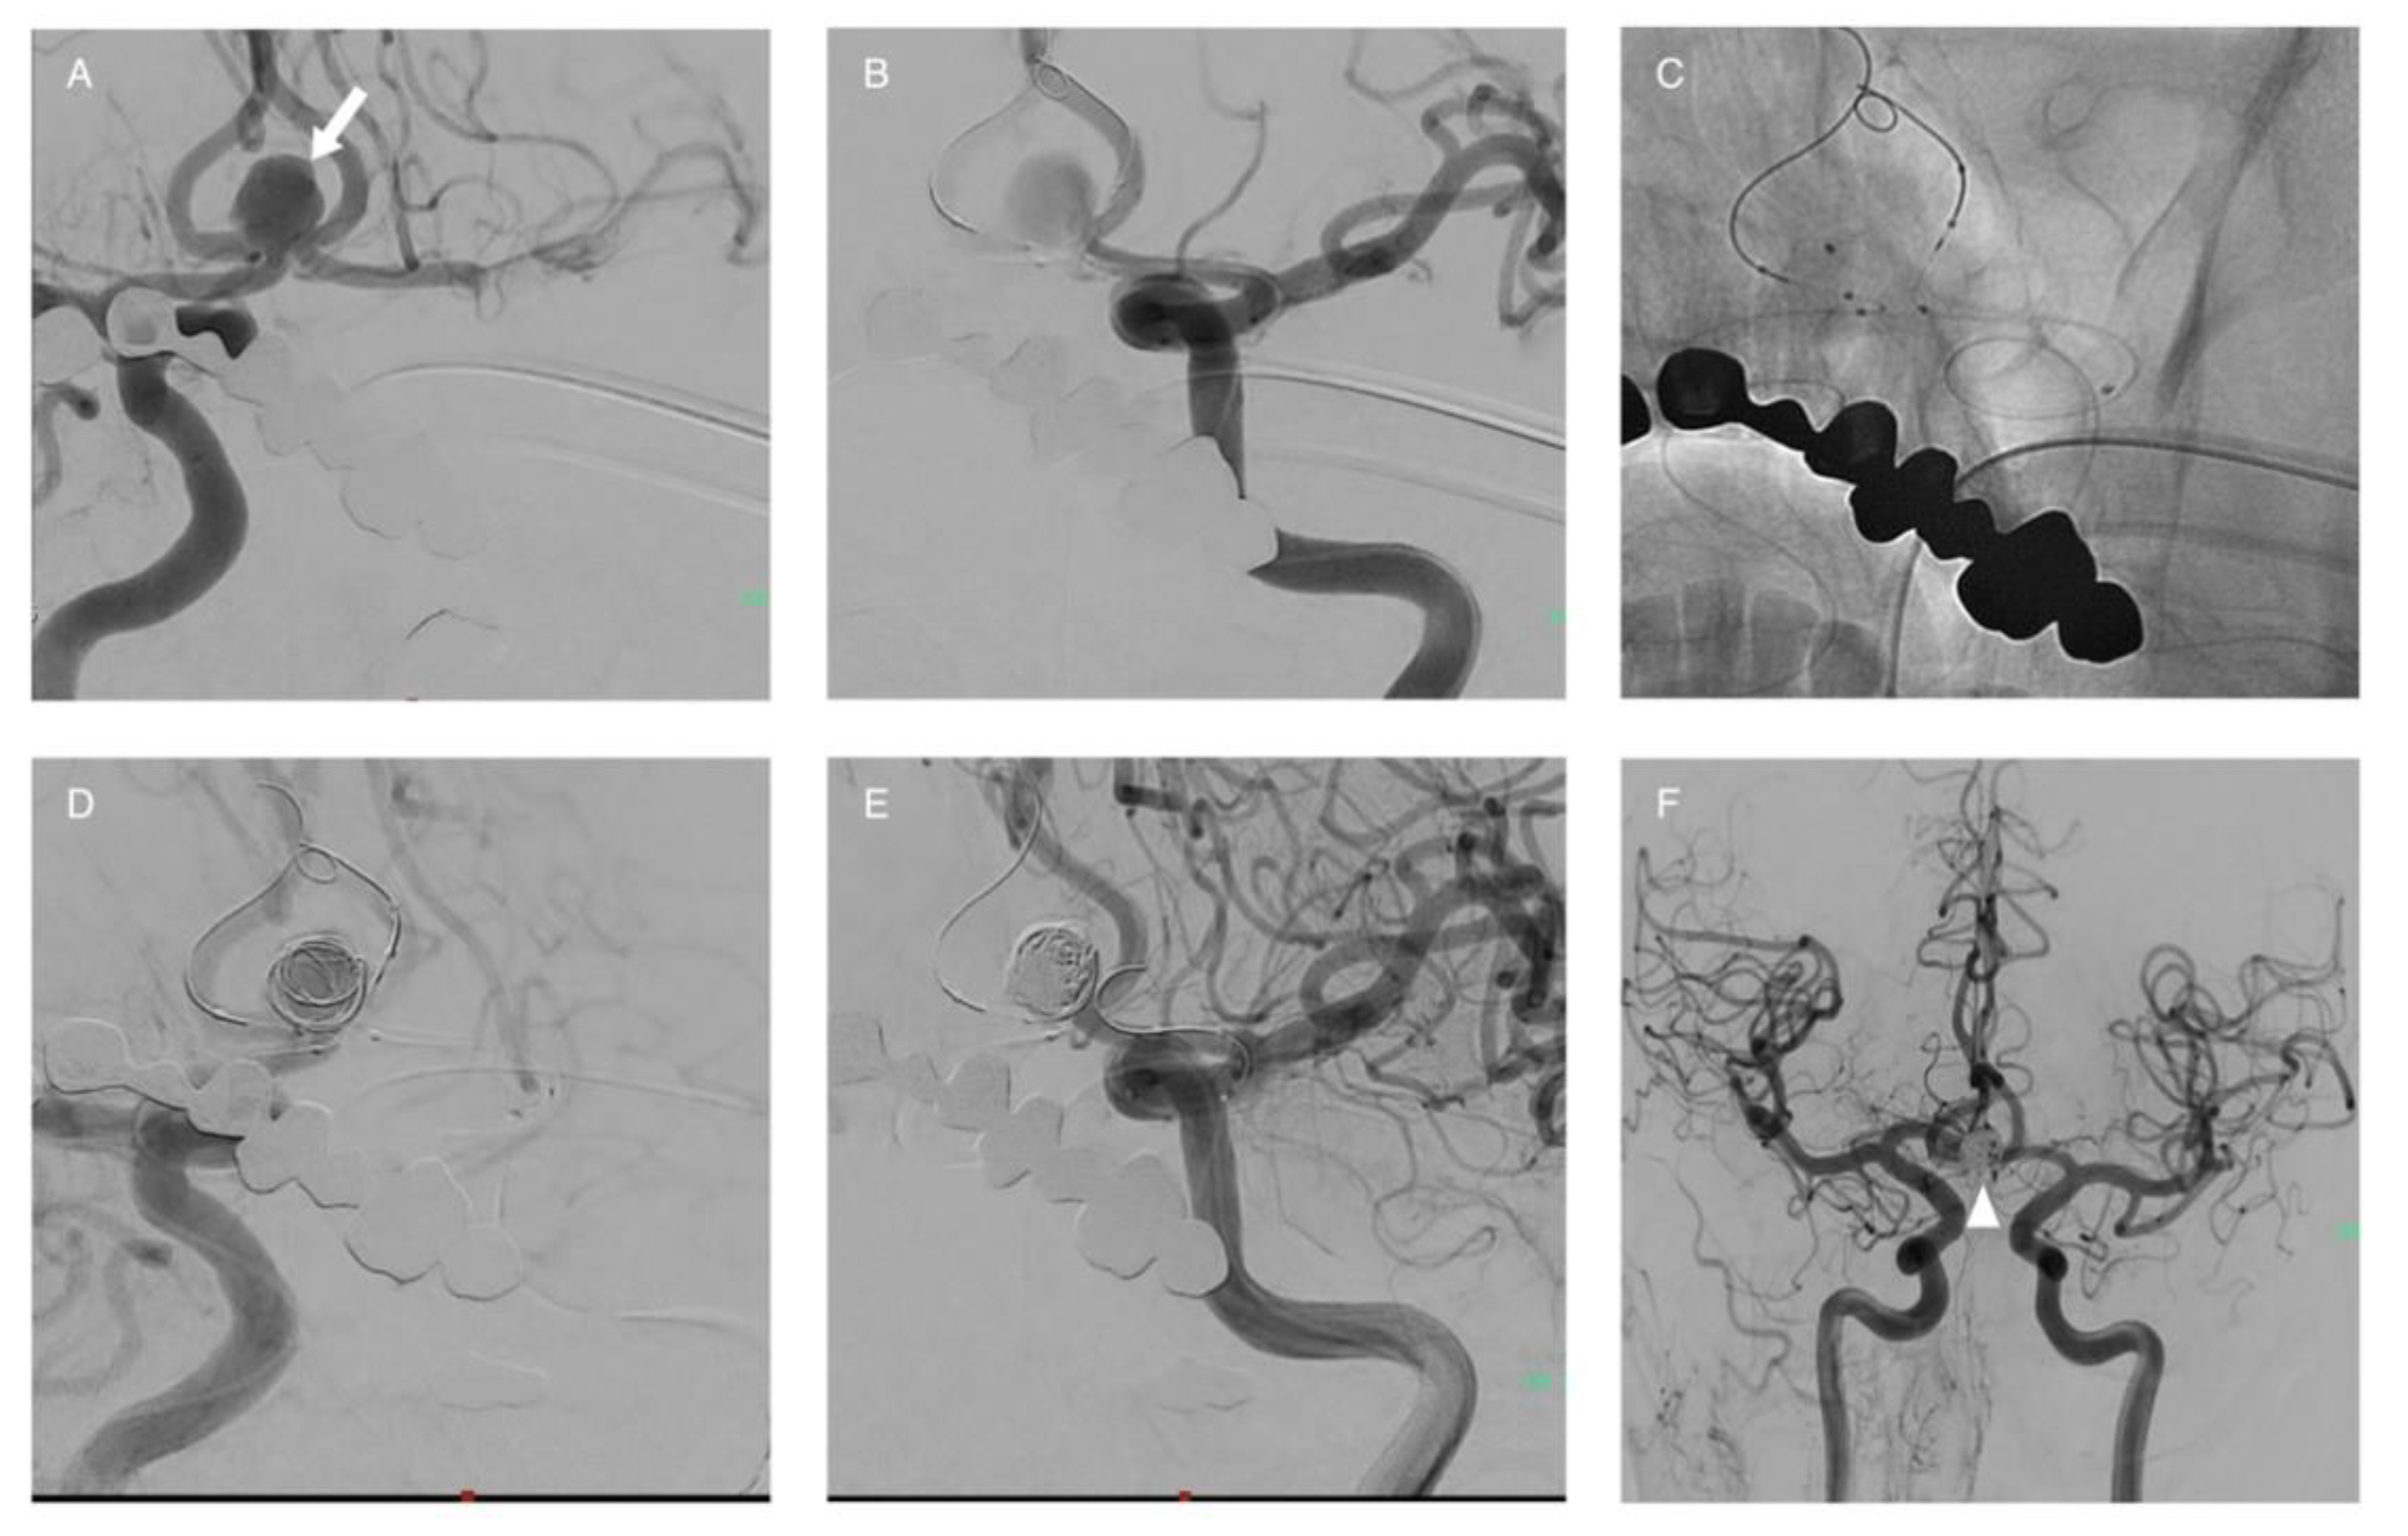

3.3. Stent-Assisted Coiling (SAC)